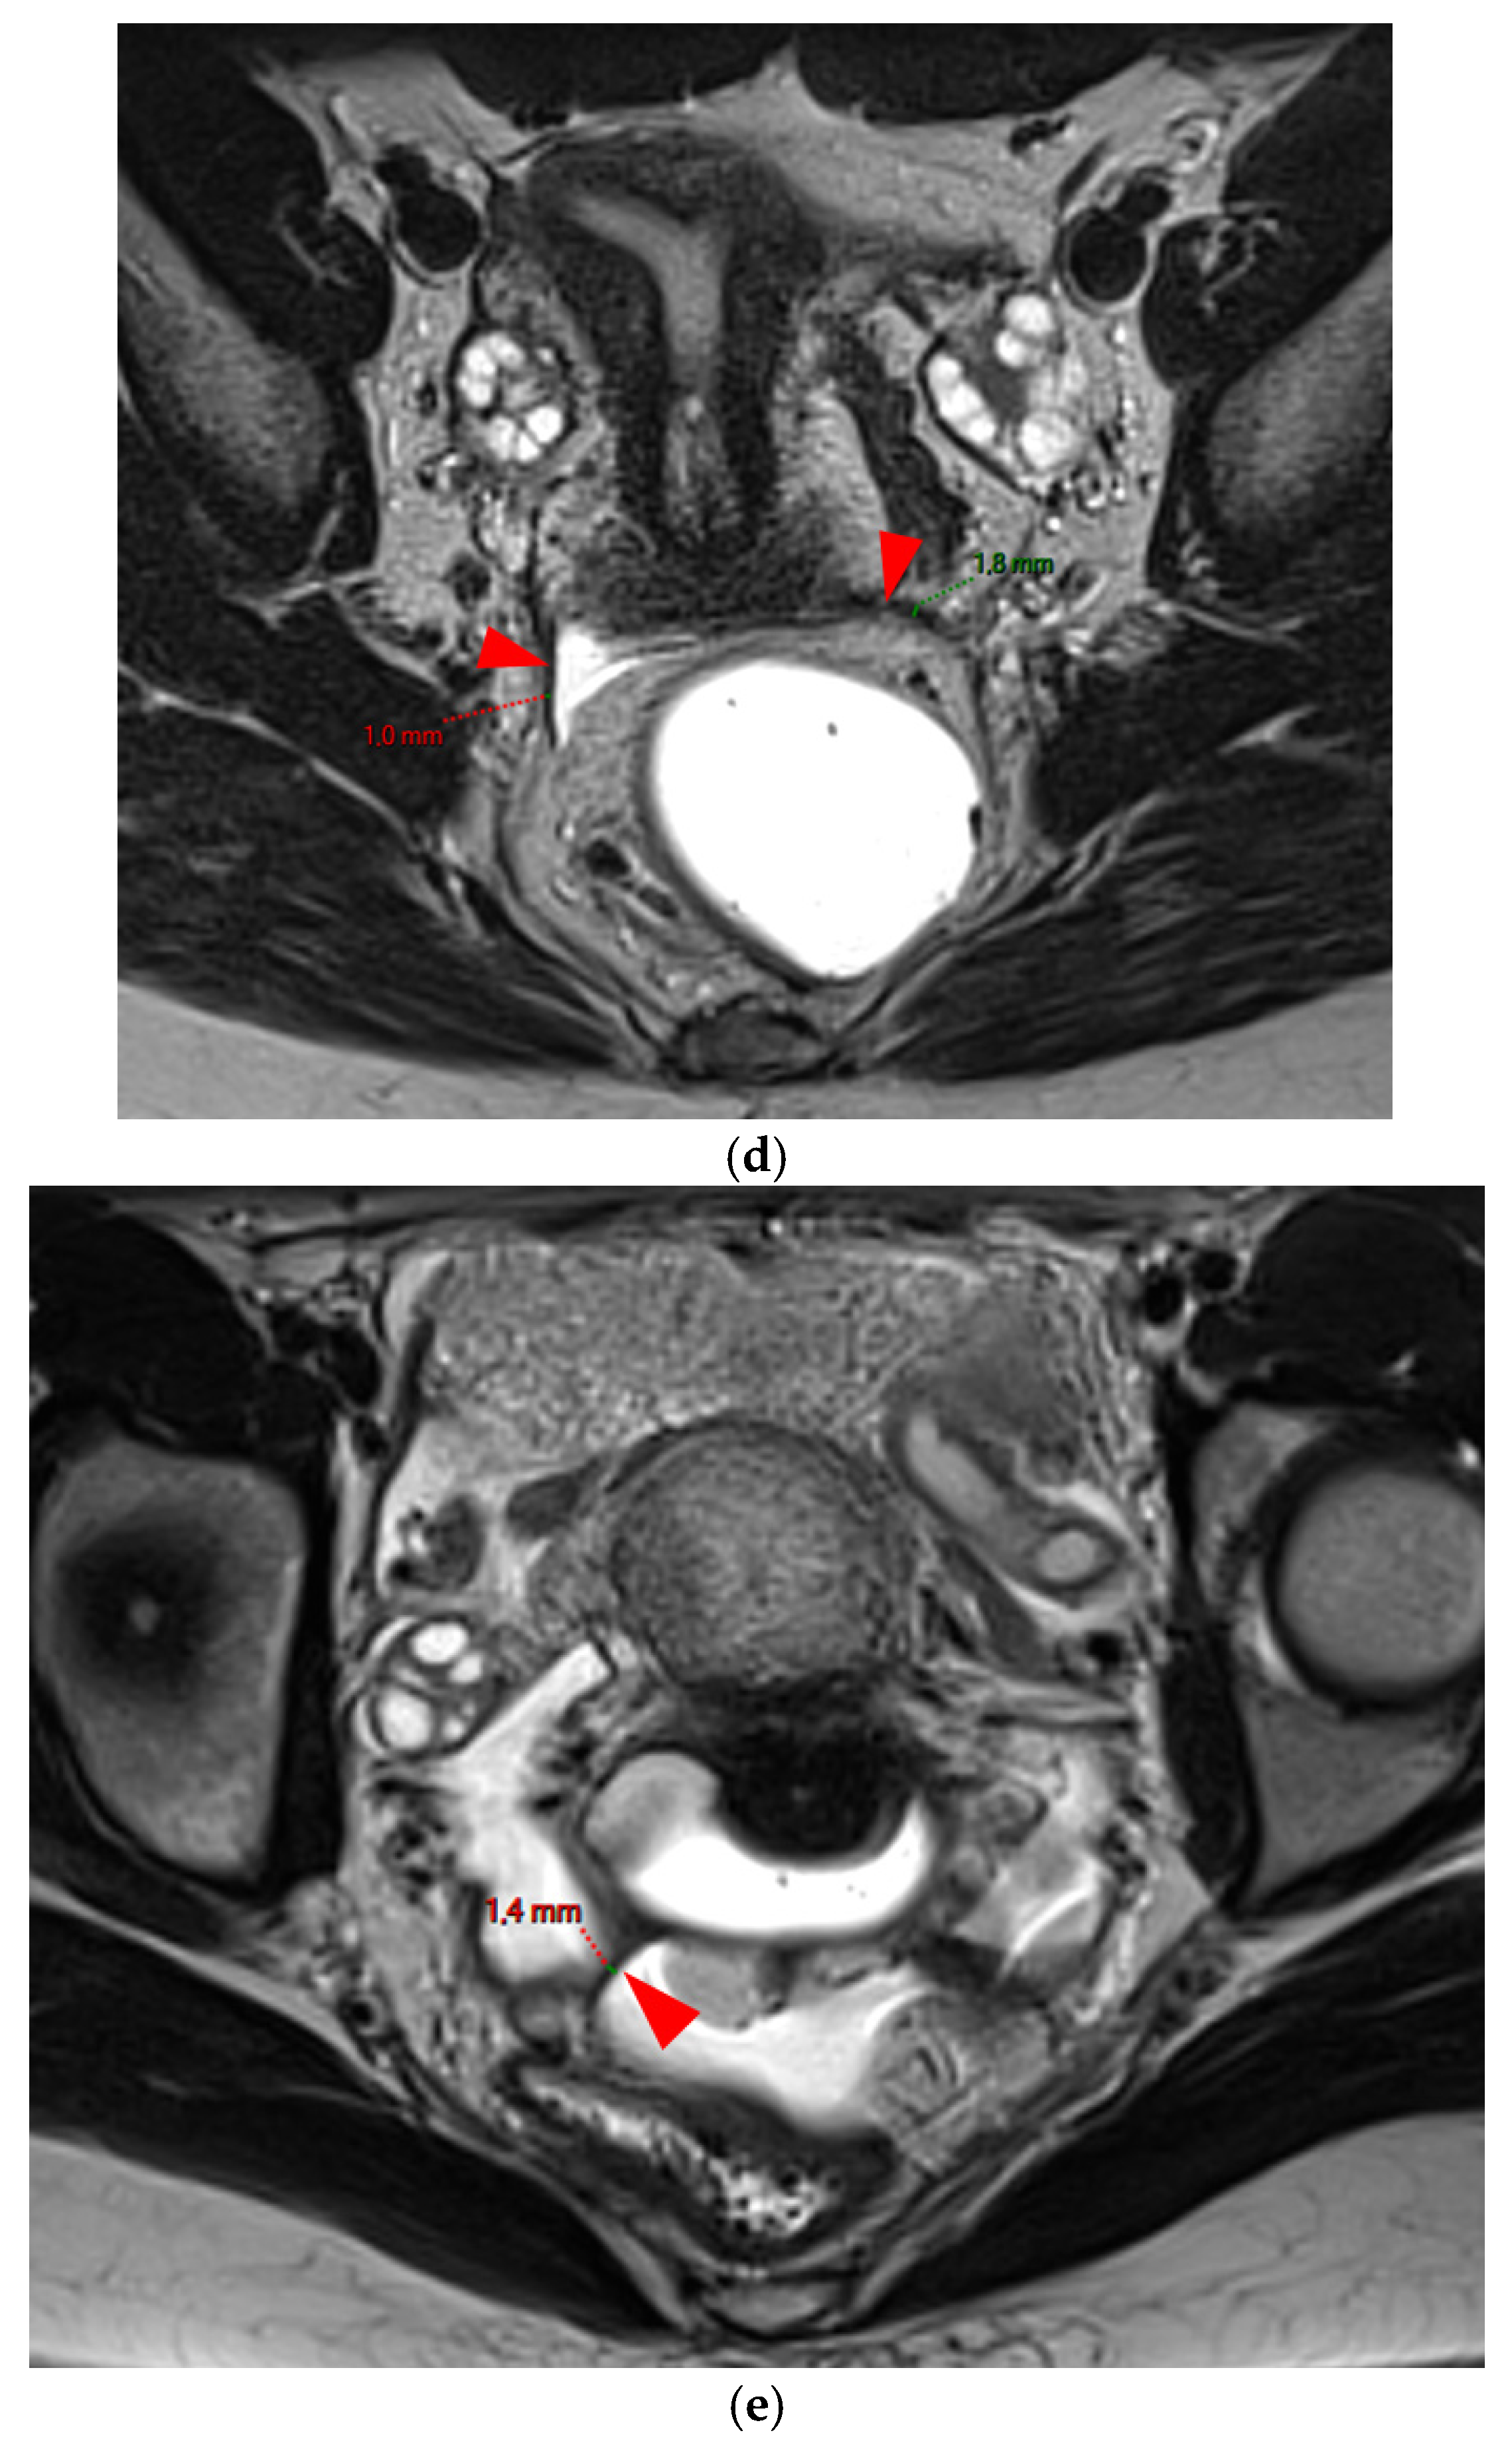

Figure 2. Pelvic MRI scans of five patients with visible but thin (≤2 mm), smooth, and regular USLs (HTD type 2). (a) Sagittal T2WI: right USL (arrowhead). (b) Sagittal T2WI: right USL (arrowhead). (c) Axial T2WI: right USL (arrowhead). (d) Axial T2WI: left and right USLs (arrowheads). (e) Axial T2WI: right USL (arrowhead).

A type 2 USL (Figure 2) is visible on MRI scans as a curvilinear T2 hypointense structure that mainly originates from the posterior uterine wall at the uterocervical junction, where the torus uterinus is located, and courses dorsocranially toward the sacrum. A type 2 USL is either visible but not measurable due to its minimal thickness (i.e., ≤1 mm), or visible and measurable but thin (i.e., between 1 mm and 2 mm, inclusive of 2 mm). It appears smooth with regular margins and often displays a longitudinally tapering shape.